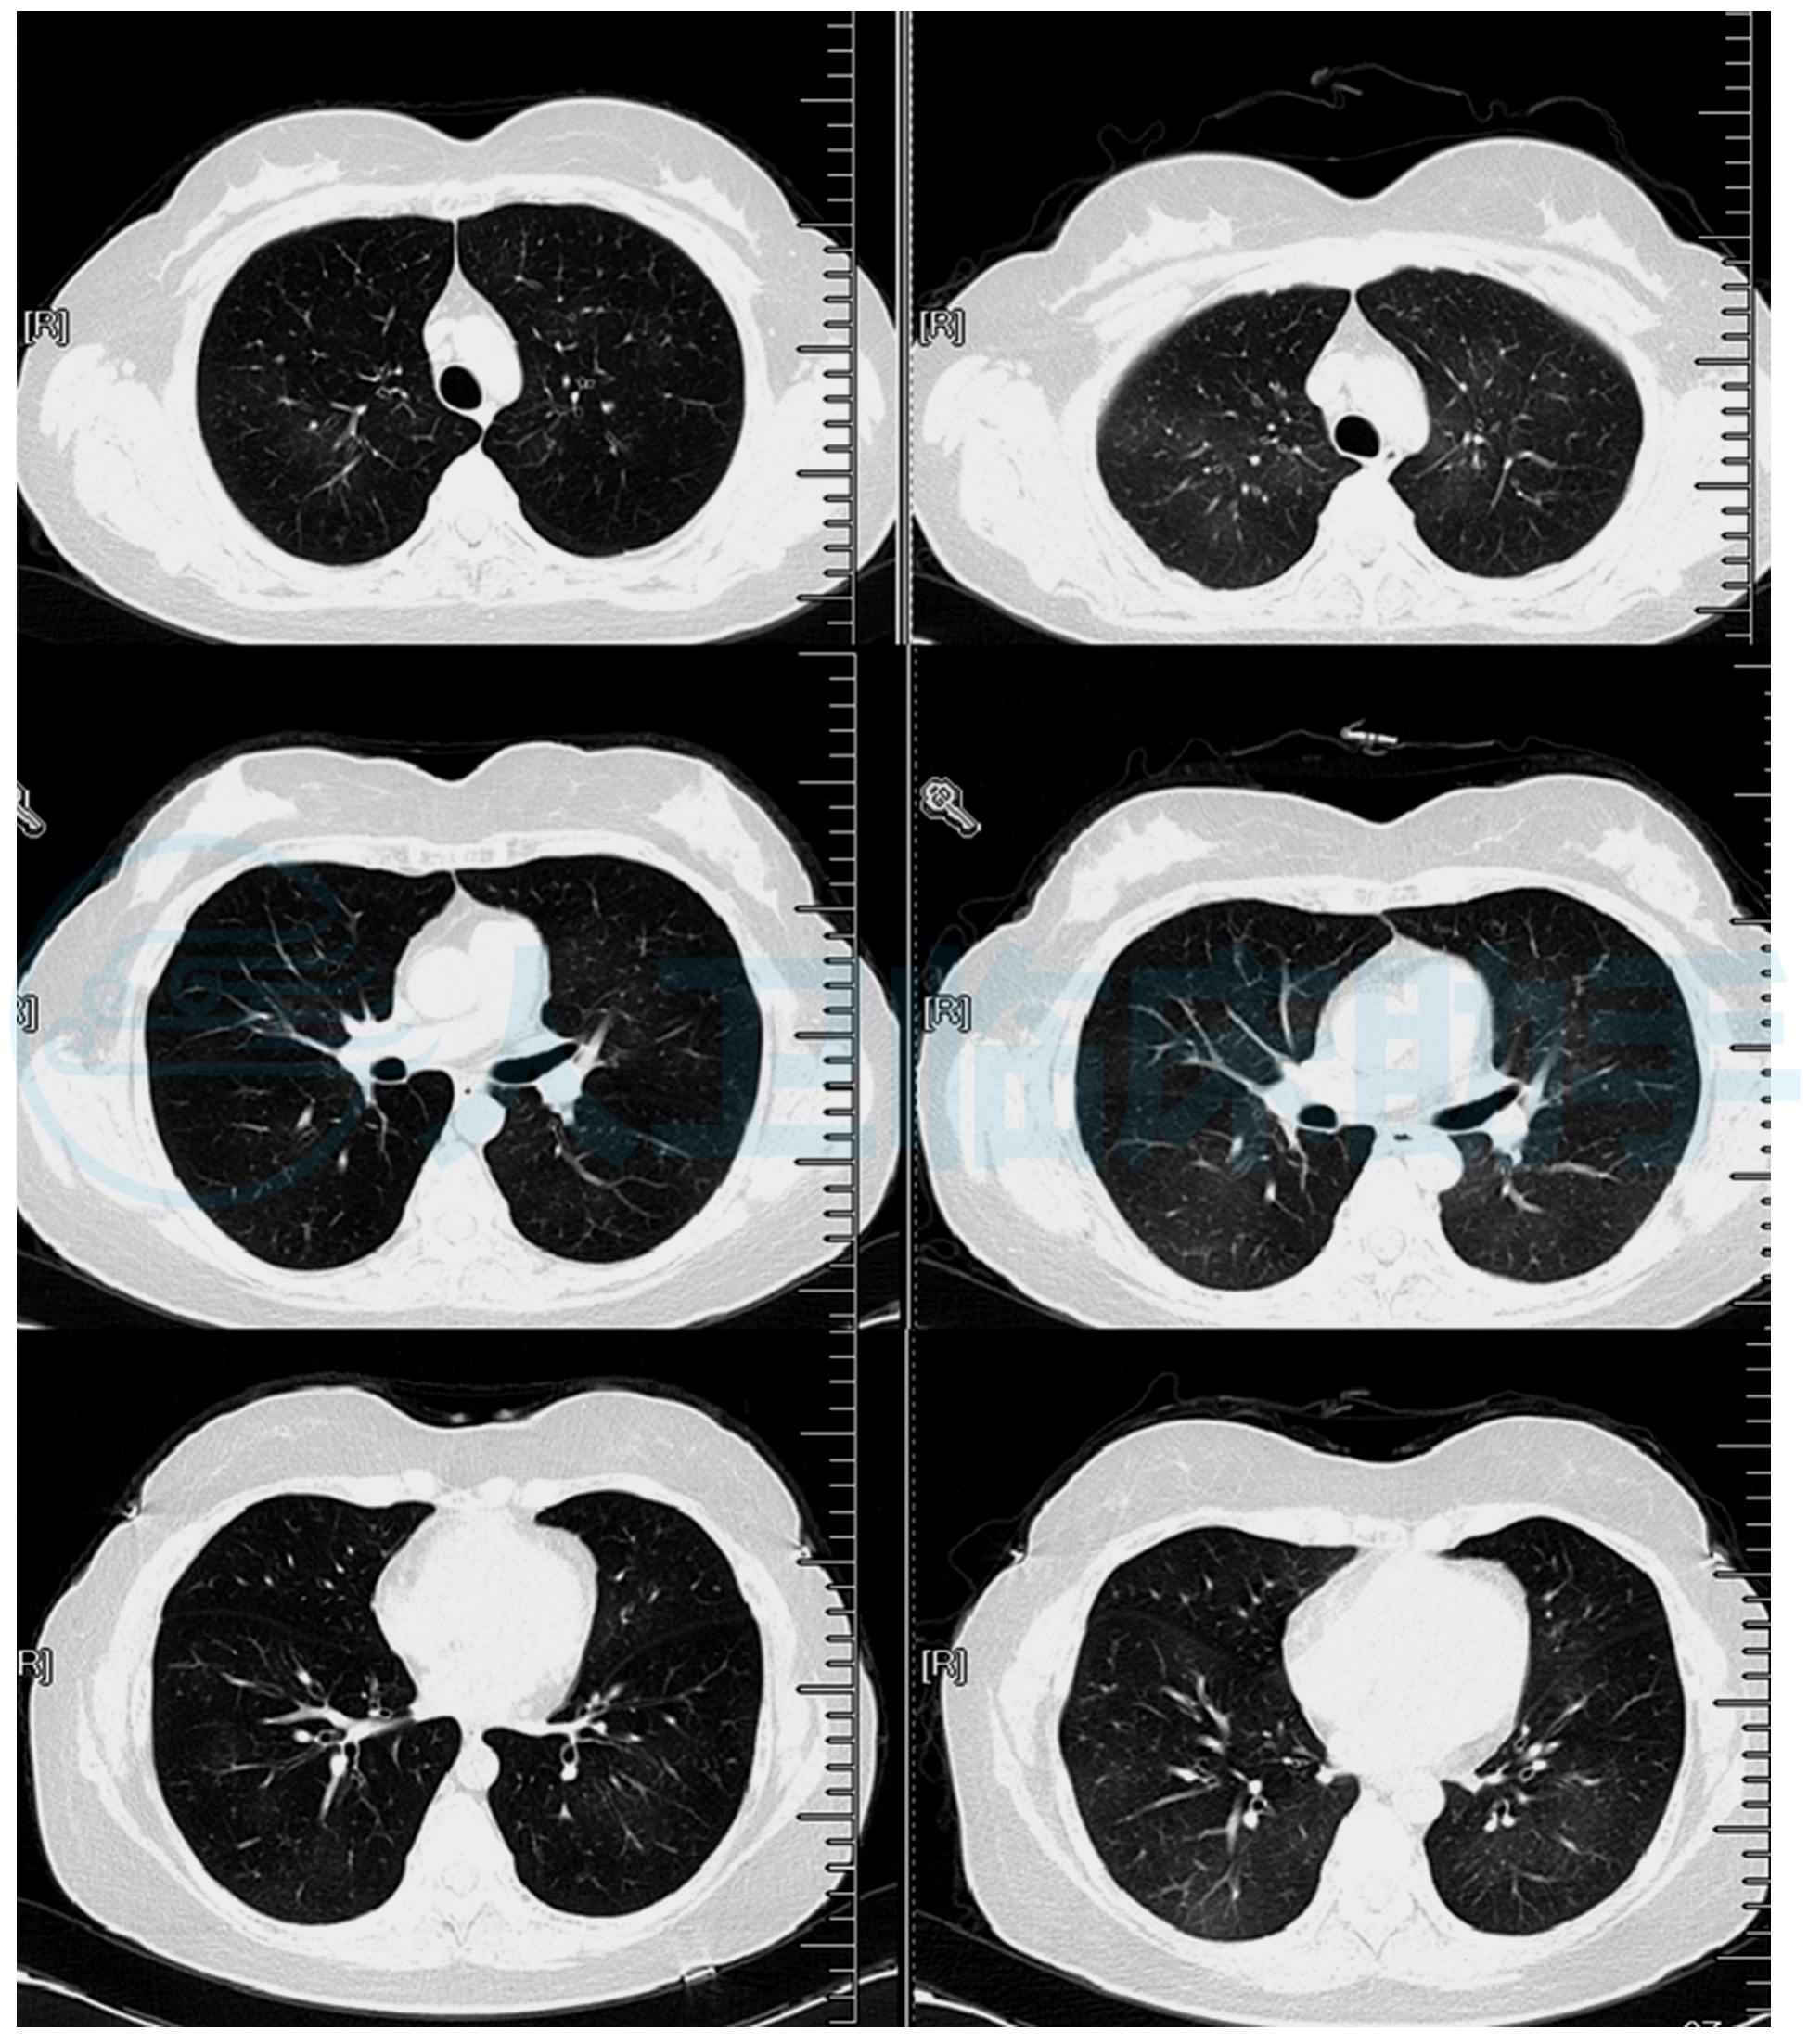

医生科普揭秘双肺纹理增粗

双肺纹理增多 影像显示肺部血管和支气管纹理较正常更为密集,可能与